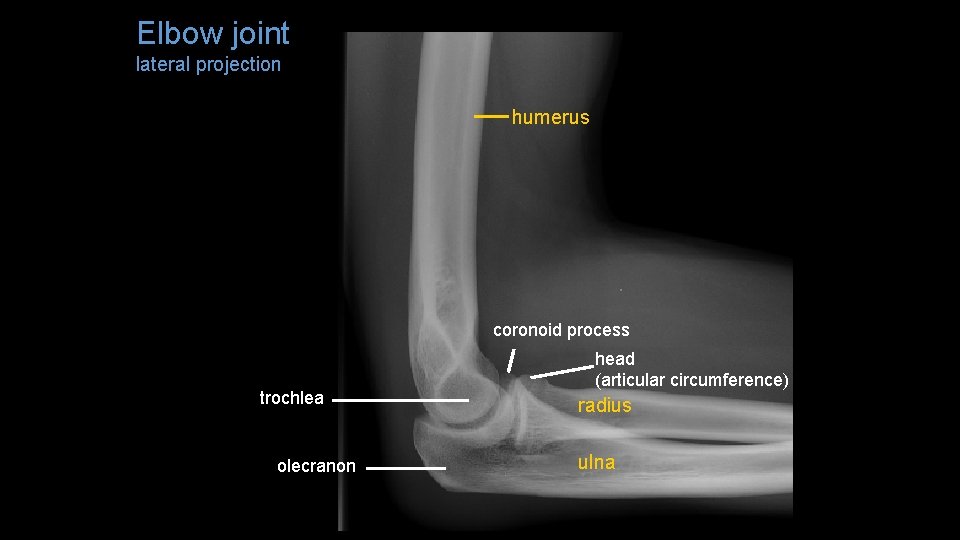

Elbow joint lateral projection humerus coronoid process trochlea olecranon head (articular circumference) radius ulna